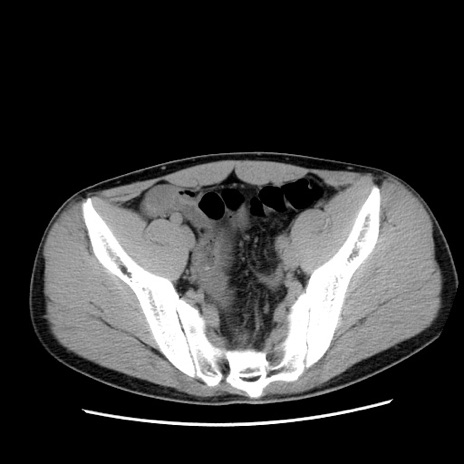

症例36(横断像)

【症例】20歳代 男性

【主訴】心窩部痛

【現病歴】今朝より上腹部痛あり。一旦軽快していたが再度出現したため救急要請。昨日夕に白身の魚を含む刺身を食べた。

【身体所見】BP 136/89mmHg、HR 74/min、BT 37.0℃、腹部:膨満、軟、心窩部に圧痛あり。反跳痛なし、筋性防御なし、腸雑音やや亢進あり。

【データ】WBC 17700、CRP 0.48